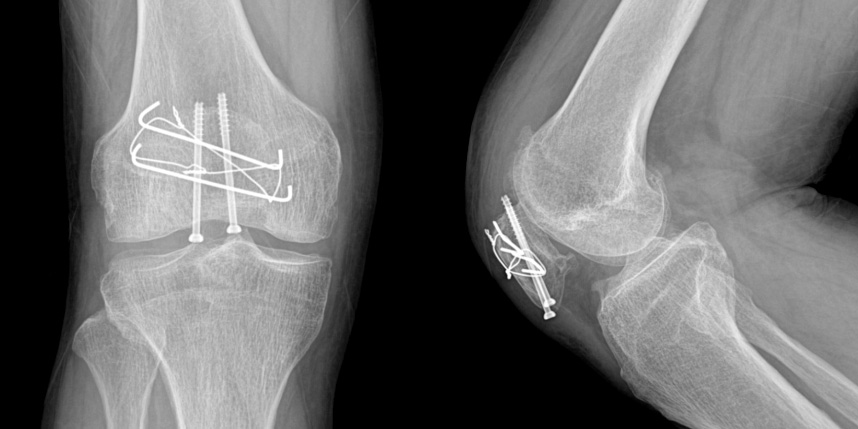

무릎 골절

골절은 정확하게 골절편을 잘 맞추고 고정하는 것이 중요합니다. 특히 관절면을 잘 맞추는 것이 중요합니다.

또한 수술 이후 빠른 재활을 통해 전체적인 회복을 도모하여 일상으로 빨리 복귀할수 있도록 해야 합니다.